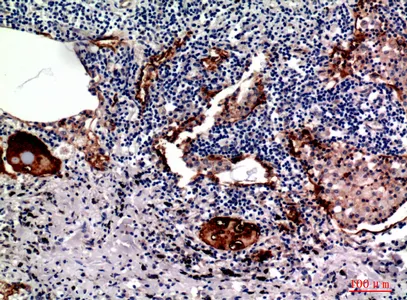

P-Selectin Rabbit Polyclonal Antibody

Cat: APRab16595

Size1:50μl Price1:$118

Size2:100μl Price2:$220

Size3:500μl Price3:$980

Size2:100μl Price2:$220

Size3:500μl Price3:$980